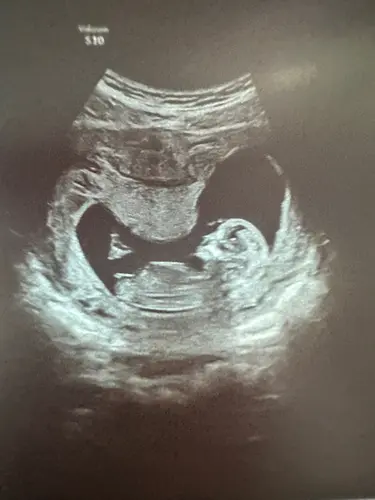

Wat denken jullie meisje of jongen?

We zullen het pas zeker weten bij de geboorte, maar mijn schoonzusje hield zich bezig met de theorieën en nu ben ik wel benieuwd wat anderen denken

Ik weet niet goed of de nub hier te zien is…

Ik zelf zie hem ook niet echt maar ook te weinig verstand van ik zal nog eens een andere erbij zetten van dezelfde echo

Oeh lastig, ik zie wel een nub maar vind het lastig om te zien of deze nu meer in een driehoek staat tov de ruggengraat of dat het recht door loopt 😅. Misschien zijn er kenners die het zien?